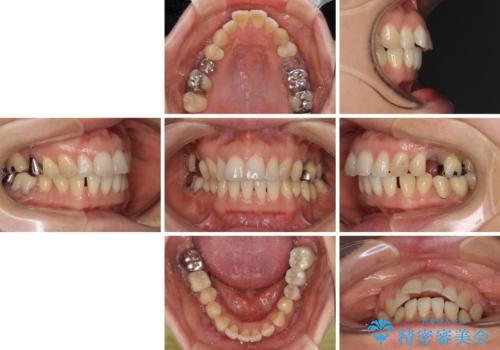

- 飛び出した上顎前歯と正中のズレを気にして来院された患者様です。

上顎正中が右側にずれていたので、むし歯が酷く抜歯が必要な左側臼歯を抜歯して正中を改善することとしました。

左下には新しいセラミックのブリッジが装着されていたため、ブリッジを壊さずに改善できるところまで咬み合わせを改善していくこととしました。

右上小臼歯は銀歯が装着されており、ワイヤー矯正の装置が装着できないため、事前に仮歯に変えてから矯正治療を行い、その後オールセラミッククラウンにて補綴治療を行いました。